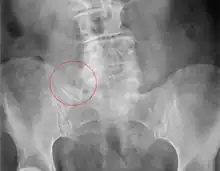

X-ray of Bertolotti's syndrome (in this case, right transverse mega-apophysis of L5 with pseudoarticulation with the sacral ala). Woman 67 years old.

Bertolotti's syndrome is characterized by sacralization of the lowest lumbar vertebral body and lumbarization of the uppermost sacral segment. It involves a total or partial unilateral or bilateral fusion of the transverse process of the lowest lumbar vertebra to the sacrum, leading to the formation of a transitional 5th lumbar vertebra. Of importance is that this syndrome will result in a pain generating 4th lumbar disc resulting in a "sciatic" type of a pain correlating to the 5th lumbar nerve root. Usually the transitional vertebra will have a "spatulated" transverse process on one side resulting in articulation or partial articulation with the sacrum or at time the ilium and in some cases with both. This results in limited / altered motion at the lumbo-sacral articulation. This loss of motion will then be compensated for at segments superior to the transitional vertebra resulting in accelerated degeneration and strain through the L4 disc level which can become symptomatic and inflame the adjacent L5 nerve root resulting in "sciatic" or radicular pain patterns. Scoliosis is frequently found to be associated.[4]